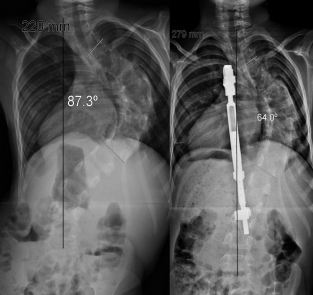

X-ray before and after corrective surgery for a 90° scoliosis